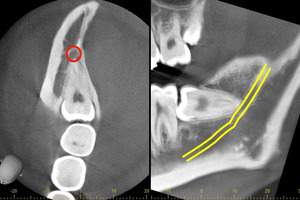

CTの画像です。下歯槽神経と親知らずはほんの少し接触していることがわかります。そのため、この親知らずは2回に分けて抜いていくことにしました。1回目は歯の頭の部分だけを切るだけになります。2回目は1−3ヶ月経ってから行います。

1回目で頭の部分を取ったスペースに歯が伸びてきますので、下歯槽神経と離れたかどうかを再びCTで確認して、残りの根の部分を抜いていく方法になります。

麻布十番歯科でのCT画像。親知らずの生え方を確認し2回に分けて抜歯を行う方法を選択

1回目から3ヶ月経ってからCTを撮影したものです。下歯槽神経の位置が根の先端から離れているのが確認できます。これで下歯槽神経を損傷させることなく、親知らずの抜歯を行うことができます。